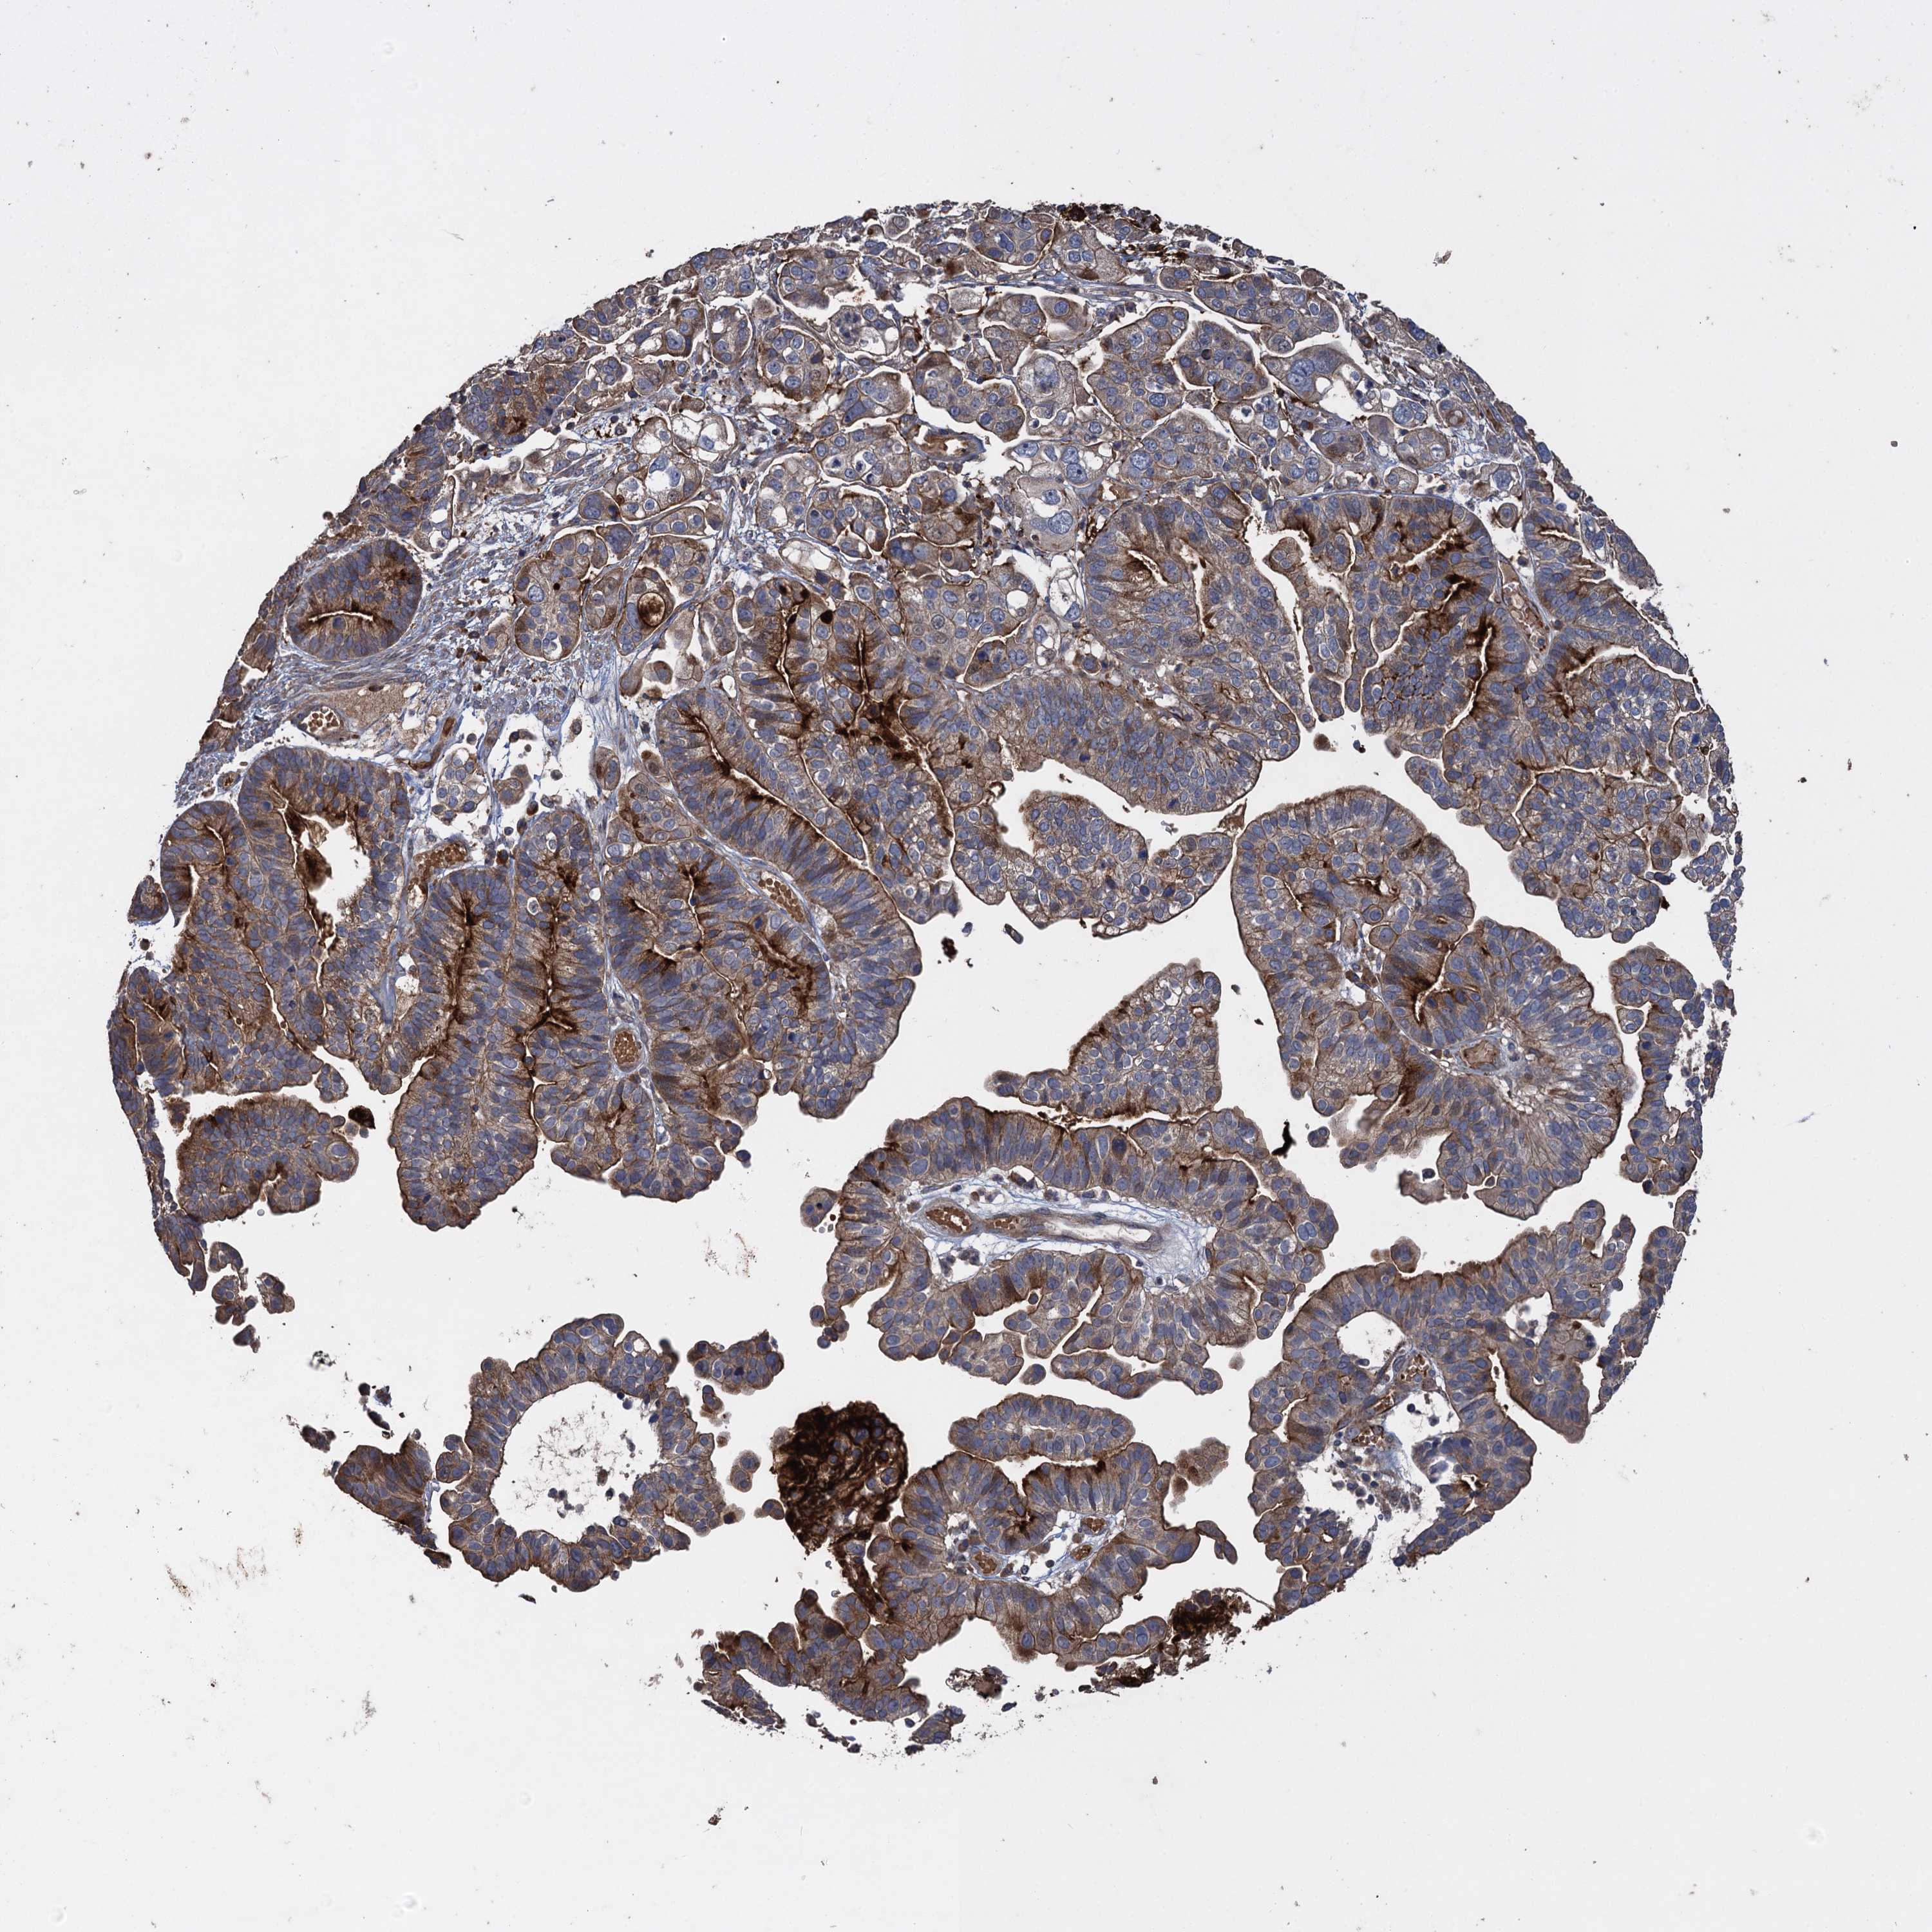

OVARIAN CANCER - Protein expressioni

A mouse-over function shows sample information and annotation data. Click on an image to view it in a full screen mode. Samples can be filtered based on level of antibody staining by selecting one or several of the following categories: high, medium, low and not detected. The assay and annotation is described here.

Note that samples used for immunohistochemistry by the Human Protein Atlas do not correspond to samples in the TCGA dataset.

Antibody stainingi

Antibody staining in the annotated cell types in the current human tissue is reported as not detected, low, medium, or high, based on conventional immunohistochemistry profiling in selected tissues. This score is based on the combination of the staining intensity and fraction of stained cells.

Each image is clickable and will lead to virtual microscopy that enables deeper exploration of all samples and also displays staining intensity scores, fraction scores and subcellular localization as well as patient and tissue information for each sample.

Antibody HPA041174

Antibody HPA041390

Cystadenocarcinoma, serous, NOS

Carcinoma, endometroid

Cystadenocarcinoma, mucinous, NOS

Carcinoma, NOS